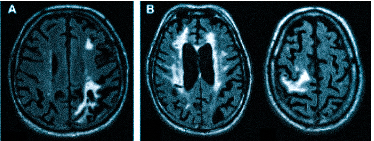

Что покажет МРТ при мигрени? Приступ мигрени сопровождается расширением сосудов мозга, за которым следует резкий болезненный спазм. МР-томограф фиксирует нарушения кровотока и выявляет ишемические очаги, которые могут появляться в большом количестве.

При диагностике может быть назначено МРТ головного мозга для проверки сосудистых патологий. Мигрень возникает из-за временного сужения сосудов в мозге, что приводит к спазму. МРТ позволяет выявить нарушения кровотока и ишемические изменения.

Множественные ишемические очаги при сосудистой деменции на МРТ: отсутствие памяти на недавние события и неадекватное поведение не являются нормой для пожилых людей. Своевременная диагностика деменции и патогенетическая терапия могут замедлить прогрессирование болезни.